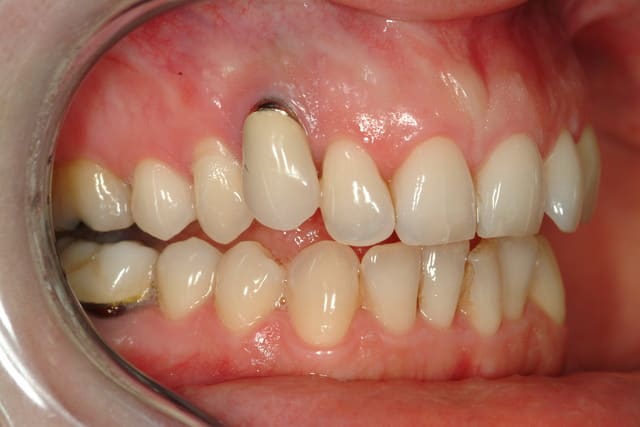

Patiente, 35 ans, d'un correspondant, reçue cet après midi.

Implant sur la 13 posé il y'à 15 ans.

La 13 était dans le palais, extraite qqs mois avant l'implantation.

problème esthétique depuis le départ...

Il me semble que c’est le liserai du pilier qui est visible, que l’ajustage la couronne soit perfectible et que l’on aperçoive légèrement l’implant.

L’espace entre 12 et 14 est trop faible pour aligner la 13 qui est trop courte sur bord incisif.

Avant de faire de gros travaux j’opterai pour ta solution avec un pilier sur mesure en zircone voir teinté en rose.